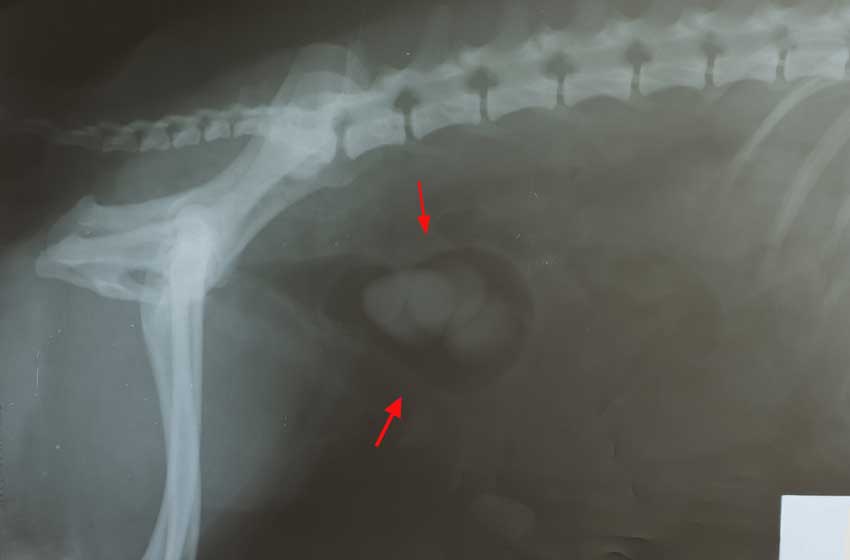

Bác sĩ thú y sẽ cẩn thận cảm nhận bụng thú cưng, xem xét bụng có bị căng cứng. Ngoài các biểu hiện lâm sàng ra, cần phải kết hợp các phương pháp khác như: siêu âm, chụp X-quang đường hệ niệu có cản quang hay không cản quang và xét nghiệm máu, nước tiểu.

Để xác định chính xác số lượng các viên sỏi và vị trí sỏi trên đường tiết niệu, tình trạng nhiễm trùng huyết và đánh giá chức năng của thận. Những chẩn đoán này là rất quan trọng để quyết định phương pháp: điều trị nội khoa hay phải phẫu thuật.